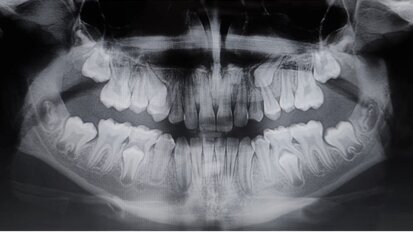

Caso di agenesia dentale trattato con impianti innovativi di diametro ridotto

Questo articolo descrive un caso di agenesia degli incisivi laterali superiori trattato mediante il posizionamento di impianti a diametro ridotto e con ...